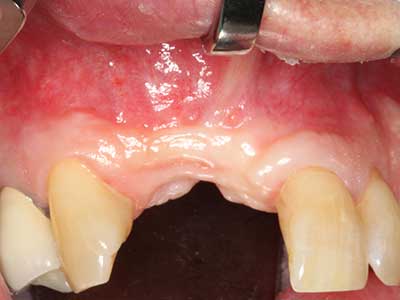

Aplicación: Partición ósea / Cortical Split

El tejido óseo no solo tiene un contenido puramente mineral, sino que también presenta una importante proporción de fibras de colágeno. Esto no solo garantiza una buena resistencia a la presión, sino también una cierta flexibilidad, que puede aprovecharse para la realización de aumentos. En la plastia de expansión clásica a efectos de una partición ósea, la cresta maxilar atrofiada se divide en su eje longitudinal y, tras alcanzar una profundidad de osteotomía suficiente, se extiende con cuidado (fig. 13-16), en un caso ideal sin desperiostizar de forma visible el maxilar (Brugnami, Caiazzo et al. 2014, Stricker, Fleiner et al. 2014). Los sistemas de tornillos y placas con distancia de expansión creciente han demostrado su eficacia para distanciar entre sí las dos tablas óseas por debajo del umbral de rotura. Por regla general, se requieren anchuras de hueso residual de al menos 3 a 4 mm (Chiapasco, Zaniboni et al. 2006) para garantizar una flexibilidad y una cobertura ósea suficientes de los implantes que van a incorporarse. En caso necesario, una osteotomía de descarga vertical unilateral o bilateral puede mejorar la flexibilidad. Como alternativa a la técnica clásica se ha descrito una combinación con otras técnicas de aumento, sobre todo en la parte bucal.

Con el uso de sierras piezoeléctricas la división se efectúa de forma especialmente cuidadosa y sin pérdidas importantes de las dimensiones, por lo que no se han encontrado diferencias significativas entre los implantes realizados en el maxilar dividido y en la cresta alveolar no deficitaria (Chiapasco, Zaniboni et al. 2006, Danza, Guidi et al. 2009). No obstante, precisamente en la partición profunda y limitada de forma local, es preciso asegurarse de que exista una adecuada irrigación por agua para evitar que se produzcan sobrecargas térmicas en las áreas de osteotomía apical.